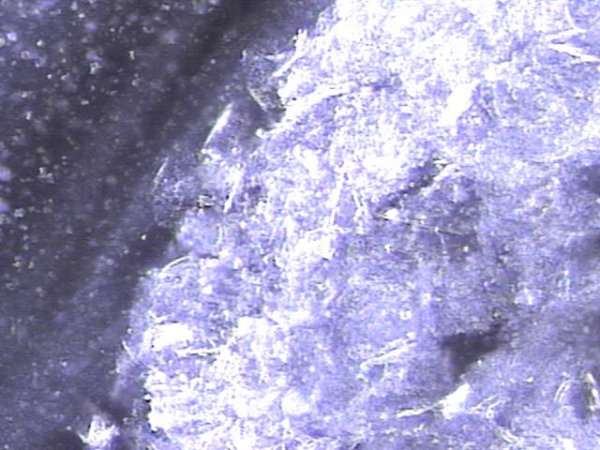

내원 첫날 전립선의 표적 치료후 치료된 정낭의 혈정액과 정자들과 염증들의 현미경학적 자료입니다.

This is a microscopic image taken after your first targeted prostate treatment, showing improvement in the seminal vesicle.

The blood-tinged fluid (hematospermia), sperm, and inflammatory cells have been successfully treated.